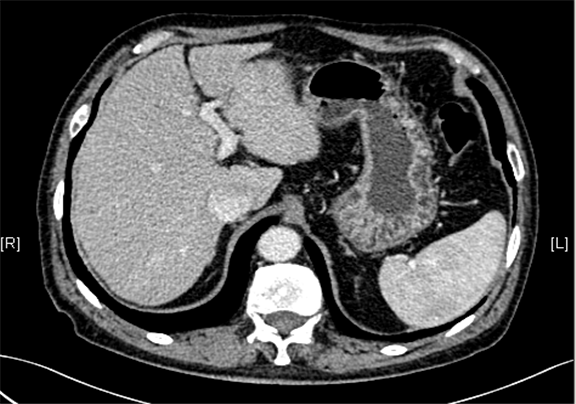

一般情况:CH-001-LT-000456, 63岁男性,身高170cm,体重77.00kg

主诉:查体发现肝占位性病变5月

现病史:患者5月前因“肝硬化”行上腹部CT发现肝占位性病变(未见报告),建议随访观察,患者无乏力、恶心、呕吐、腹胀、腹泻、血便、食欲减退,无寒战,无头痛头晕,无皮肤粘膜黄染,无尿频、尿急、尿痛、血尿。3天前再行上腹部增强CT检查示:肝左外叶占位,考虑恶性肿瘤伴门脉侵犯可能性大,建议MR平扫+强化符合肝硬化表现。双肾多发小囊肿可能性大

下腹部增强CT示:肝左外叶占位,考虑恶性肿瘤伴门脉侵犯可能性大,符合肝硬化表现。

术前CT检查:

动脉期